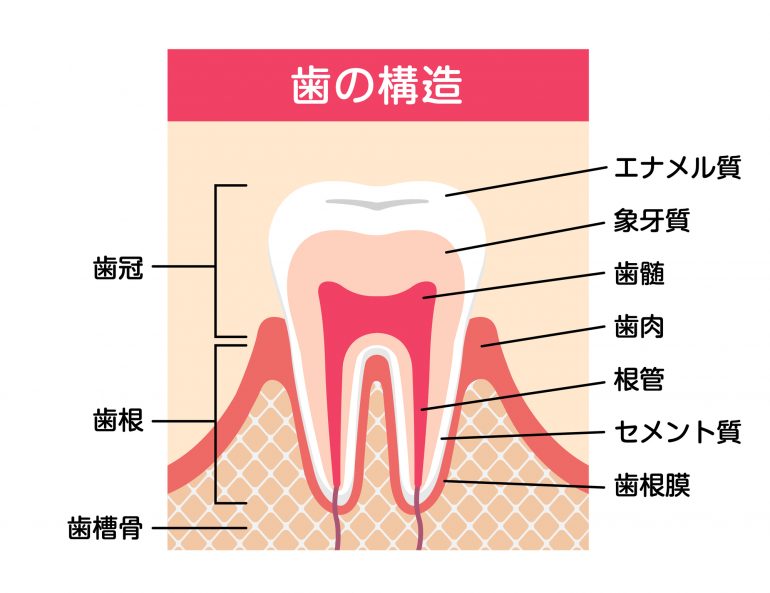

歯の構造と「むし歯」の進行

「歯」の構造は、外側から

- エナメル質

- 象牙質

- 歯髄

の3構造で成り立っています。

直接、目で確認することができる【歯冠】と、歯肉の下に隠れている【歯根】があり、歯は「歯槽骨」と「歯肉」に支えられています。